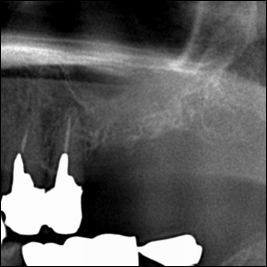

術前レントゲン写真

歯の根っこが割れているのが分かります。